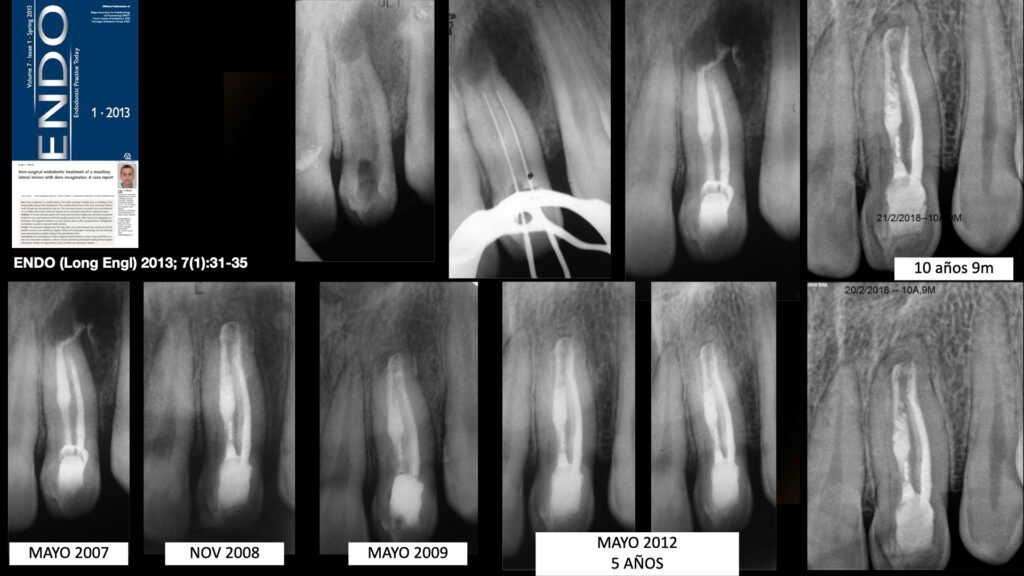

Methods: A 12-year-old male patient with severe pain and facial swelling was referred by his general dentist for root canal treatment of the left maxillary lateral incisor. After clinical and radiographic examinations, the diagnosis resulted in an acute alveolar abscess with a periapical lesion. Radiographic examination revealed an aberrant tooth anatomy.

Results: The symptoms disappeared a few days after root canal treatment was carried out and the patient’s recovery was satisfactory. Regular clinical and radiographic monitoring over the following years demonstrated complete healing of the periradicular lesion.

Conclusions: Accurate diagnosis of dens invaginatus led the clinician to clean, shape and fill this complex root canal system properly in order to achieve satisfactory periradicular healing without surgical intervention. Results are supported by 5 years of follow-up examination reviews.